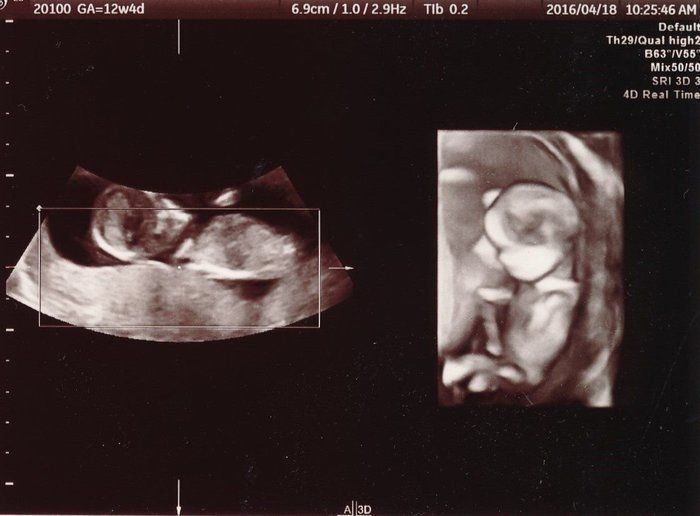

「背骨!足骨!ホントに人間がいる!」エコー画像を見る度、ゆっくり親になっていく私たち -